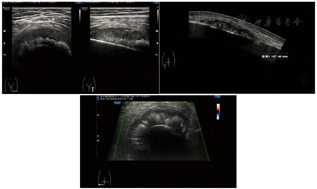

入院前查下肢彩超示:左股骨中下段骨皮质浅方实性占位。入院后查左股骨全长正侧位片示:左股骨中段骨质密度稍显减低,骨皮质毛糙、变薄,周围软组织肿胀,关节对应关系良好。查肌骨超声所见图1:左侧股骨中下段骨长轴纵切面骨皮质局部骨膜增厚,不规则隆起,可探及范围约157 mm×17 mm混合回声区,后方回声减低,交界处的骨膜回声增强、增厚、抬高呈"Codman"三角征;围绕骨干横切面见"轮辐样"放射状分布的针状强回声,回声与骨皮质表面垂直;彩超多普勒血流显像(color Doppler flow imaging,CDFI):内可探及星点状血流信号;后方骨皮质尚连续,中下段边缘毛糙。进一步查左股骨中下段增强CT所见图2:左股骨中下段髓腔内见纵形软组织密度影,邻近骨皮质稍增厚且骨质密度减低,呈筛孔样骨质破坏,周围可见放射状骨膜反应及软组织肿块,骨干未见明显膨胀,增强扫描后髓腔内见穿行血管影,周围软组织肿块中度强化。查左股骨中下段核磁见图3:左股骨干中下段髓腔内条带状长T1、压脂长T2信号影,骨皮质厚薄不均,信号欠连续,压脂信号增高,骨干周围包绕软组织块,呈略短T1、压脂长T2信号影,压脂T2其内见多发细线样低信号影垂直于骨皮质分布,病变与周围软组织区界限不清,软组织内片状长T1、压脂长T2信号影;扫描所示左股骨干远端小圆形、右股骨干中段髓腔内条带状长1、压脂长T2信号影,境界较清晰,邻近骨皮质未见明确异常。查胸部CT见图4:双肺纹理增重,双肺见多发大小不等结节样高密度影,较大者边缘欠光整,呈浅分叶状,左肺下叶见索条影,纵隔内见多发小淋巴结影;肝右叶内见类圆形低密度影,边缘可见模糊稍高密度影。腹部超声所见:肝脏实质回声致密,内可见多个低回声区,较大者大小约20 mm×14 mm的肿物;脂肪肝。查腹部ECT见肝右叶上述改变外,未见其他异常。实验室化验肿瘤标志物CEA、AFP、CA-199等都在正常范围;C反应蛋白11.43 mg/L(参考范围0.00~0.60 mg/L,以下同);碱性磷酸酶183 U/L(40~150 U/L);磷酸肌酸激酶同工酶110 U/L(1~24 U/L)。